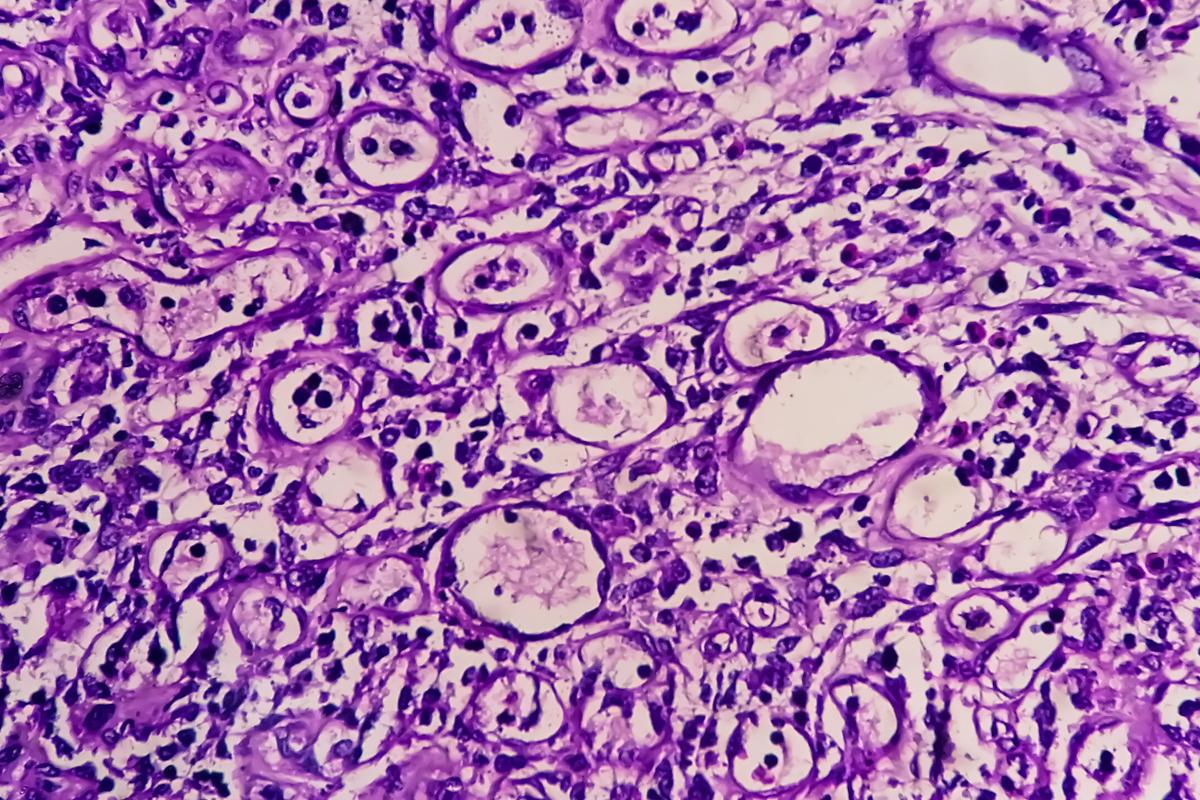

L’étude asiatique ATTRACTION-5 est une phase III ayant comparé chez 755 patients une chimiothérapie (CT) adjuvante (XELOX ou S1) seule ou en combinaison avec le nivolumab (anti-PD1) après résection (au minimum résection D2) d’un adénocarcinome gastrique ou de la JOG de stade III. Il n’y avait que 7 % de tumeur de la JOG mais 56 % de type « diffus ». L’objectif principal de survie sans récidive (SSR) n’était pas atteint (HR=0,90; 95,72 % CI, 0,69–1,18 ; p=0,436 3). Le taux de SSR à 3 ans était 68,4 % dans le groupe CT + nivolumab versus 65,3 % dans le groupe CT + placebo. Il n’y avait pas de différence en survie globale. Le profil de tolérance du nivolumab était habituel.

En analyse de sous-groupes, les patients avec tumeur PD-L1 TPS > 1 % semblaient avoir une SSR plus longue avec l’immunothérapie mais ils ne représentaient que 11 % de la population globale.